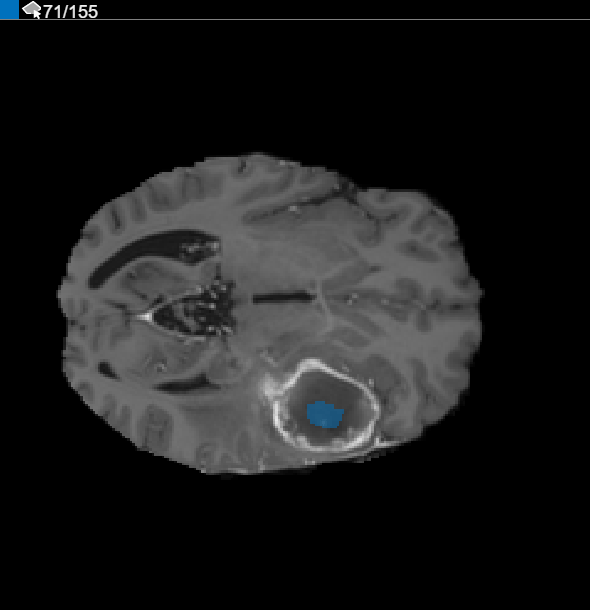

After using interpolation, check the individual slices to see if the interpolation created satisfactory ROIs. Note that the ROI on slice 71 does not fill the entire object that you want to segment. You can manually adjust the ROI using the Paint Brush tool. Alternatively, you can use one of the tools on Automate tab. For example, you can use Active Contours to grow the ROIs on the slices where it does not fill the full size of the tumor. You can also use the Add Algorithm to specify your own algorithm to operate on the ROIs.

CreateBinaryMaskUsingVolumeSegmenterExample_09.png